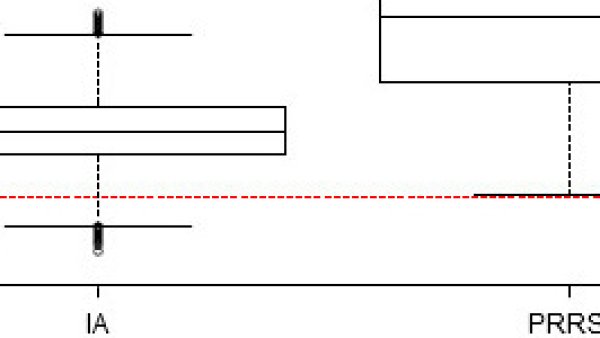

La infección con el virus de la influenza porcina y del PRRS durante la lactación se asocia con un incremento (limitado en el caso de la influenza y de mayor magnitud en el caso del PRRS) significativo en la mortalidad post-destete.